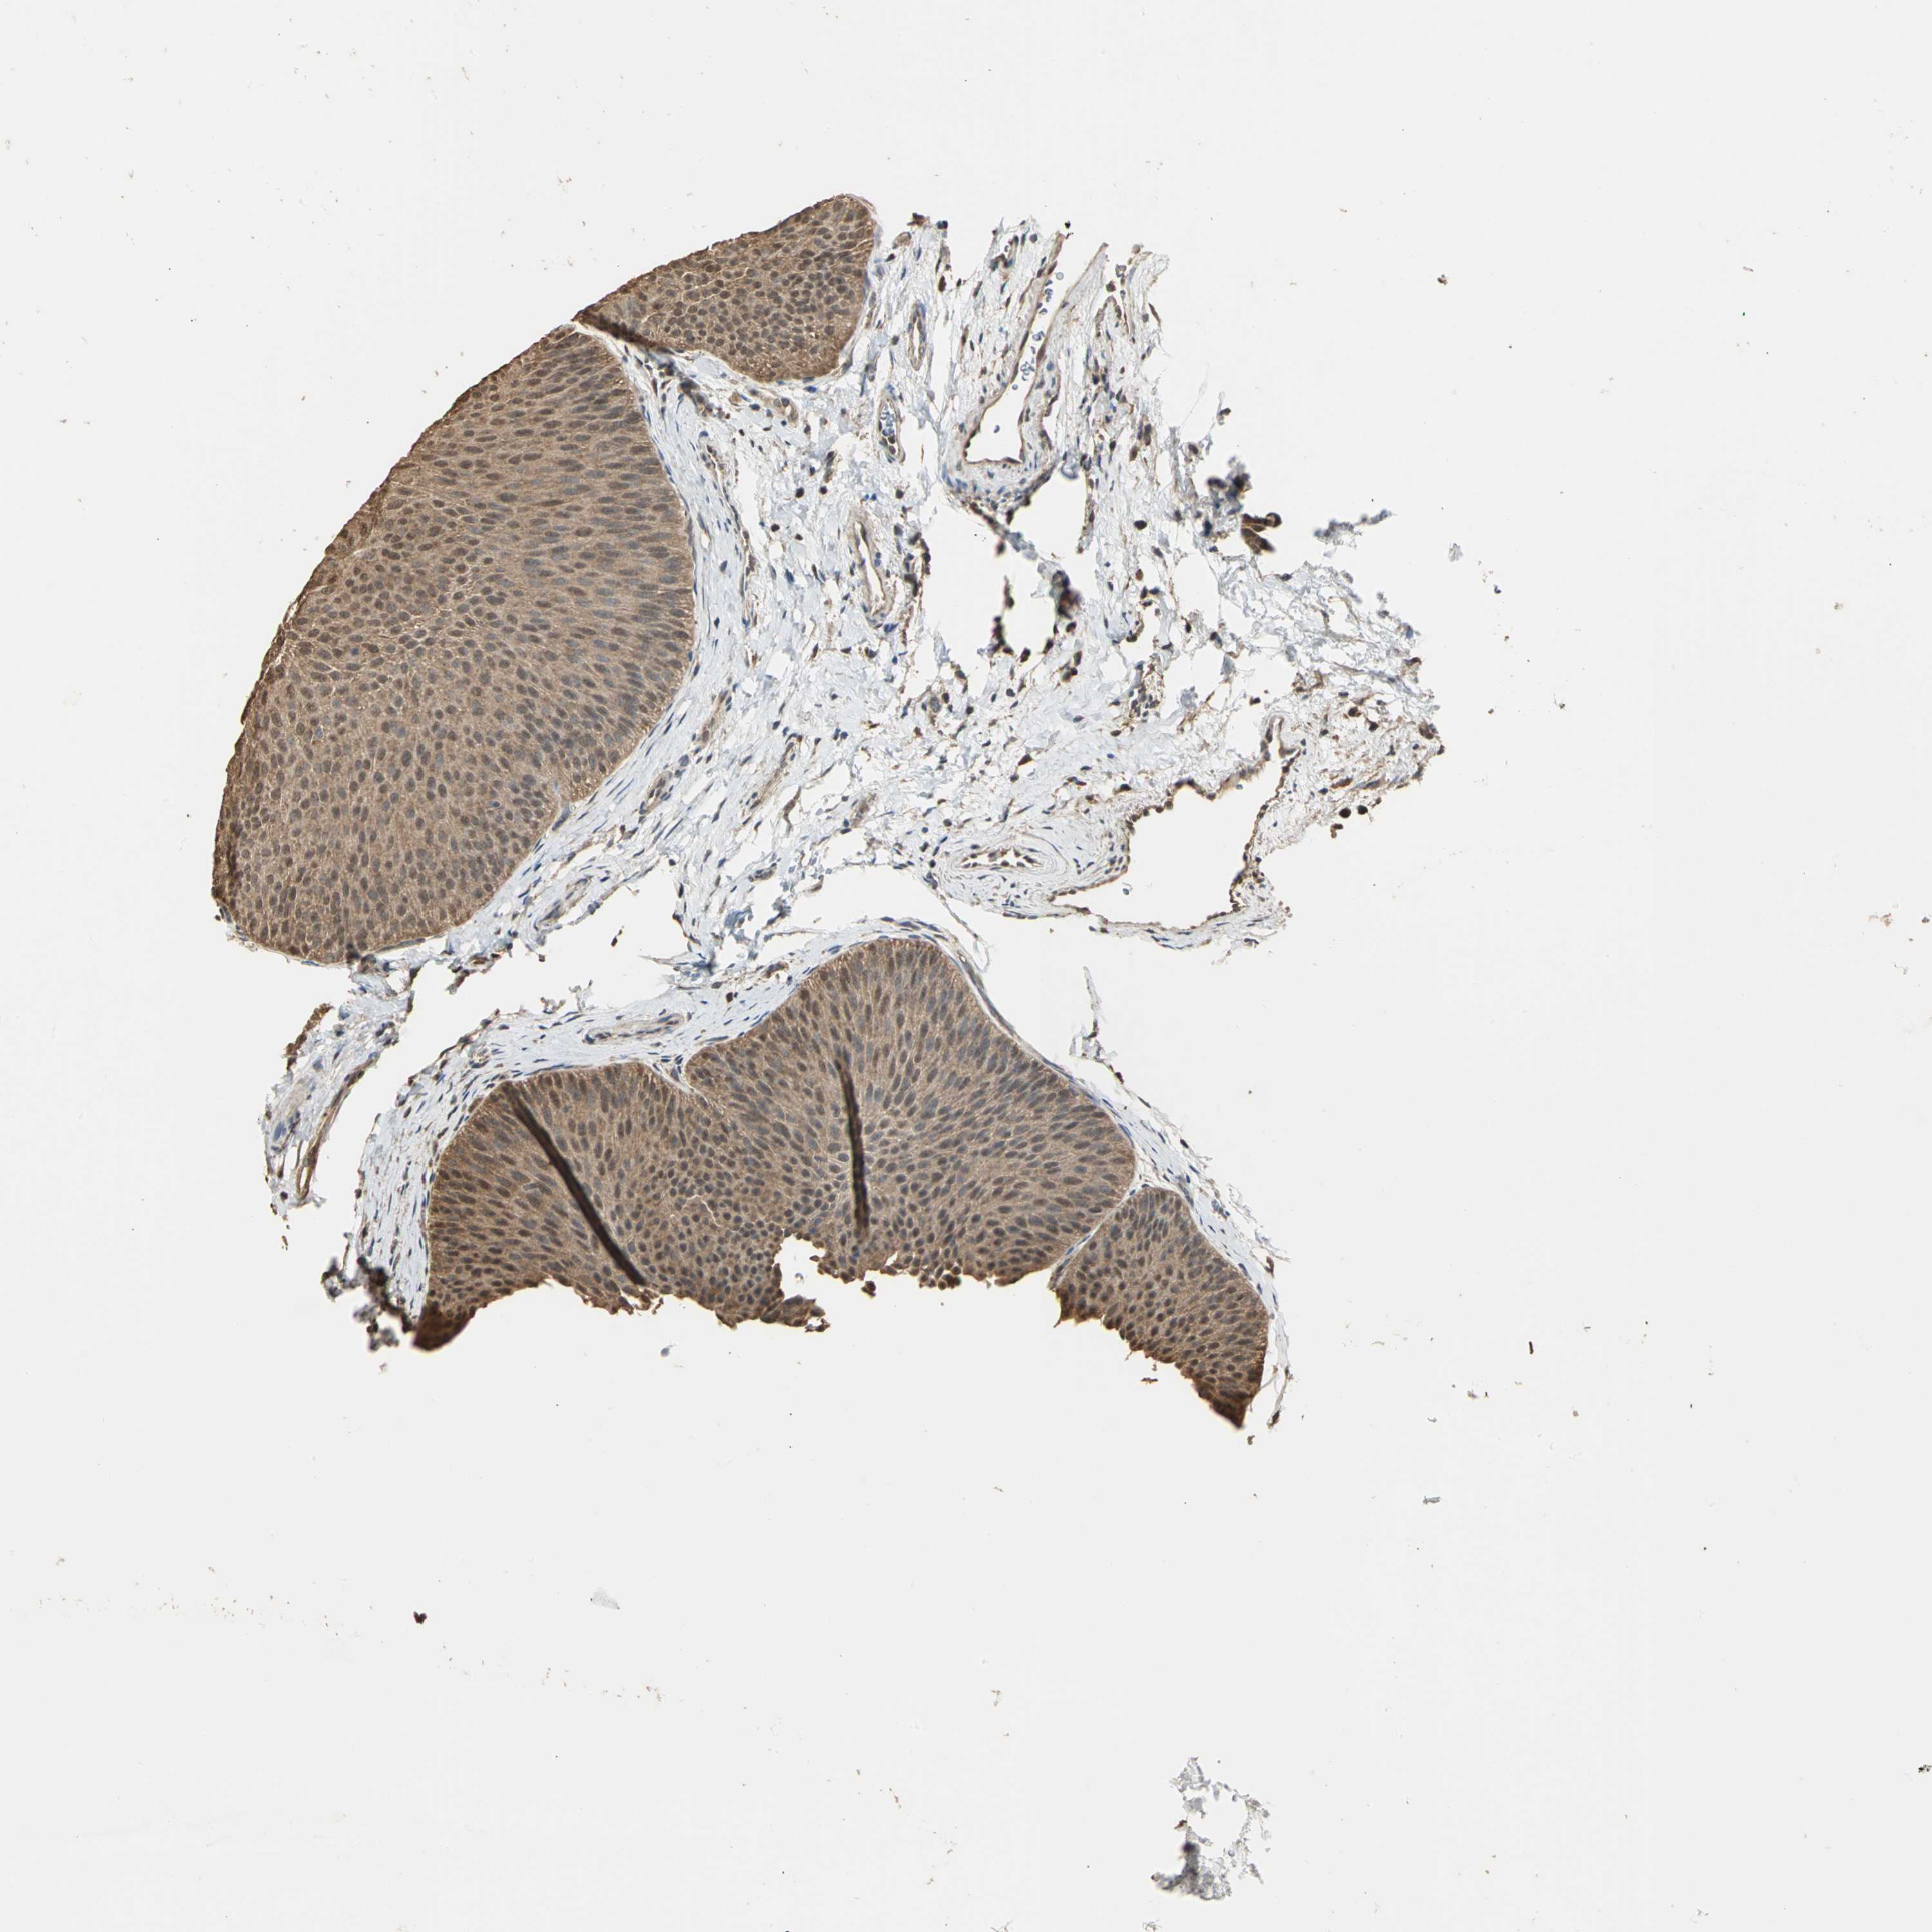

UROTHELIAL CANCER - Protein expressioni

A mouse-over function shows sample information and annotation data. Click on an image to view it in a full screen mode. Samples can be filtered based on level of antibody staining by selecting one or several of the following categories: high, medium, low and not detected. The assay and annotation is described here.

Note that samples used for immunohistochemistry by the Human Protein Atlas do not correspond to samples in the TCGA dataset.

Antibody stainingi

Antibody staining in the annotated cell types in the current human tissue is reported as not detected, low, medium, or high, based on conventional immunohistochemistry profiling in selected tissues. This score is based on the combination of the staining intensity and fraction of stained cells.

Each image is clickable and will lead to virtual microscopy that enables deeper exploration of all samples and also displays staining intensity scores, fraction scores and subcellular localization as well as patient and tissue information for each sample.

Antibody HPA004190

Antibody CAB005870

Staining

High

Medium

Low

Not detected

Intensity

Strong

Moderate

Weak

Negative

Quantity

>75%

75%-25%

<25%

None

Location

Nuclear

Cytoplasmic/membranous

Cytoplasmic/membranous,nuclear

Urothelial carcinoma, High grade

Urothelial carcinoma, Low grade